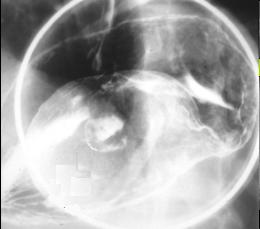

Image en

laculaire eleve intra luminale gastrique a

nultilobulaire ou epassisement de gros plis . S'il y

avait lesion ulceree en association c'est tres

difficile de diagnostic differentielle avec

anenocarcinoma de l'estoma .Image TOGD avec

compressive region antral . |

Meme cas en double de

contrast.TOGD .. |